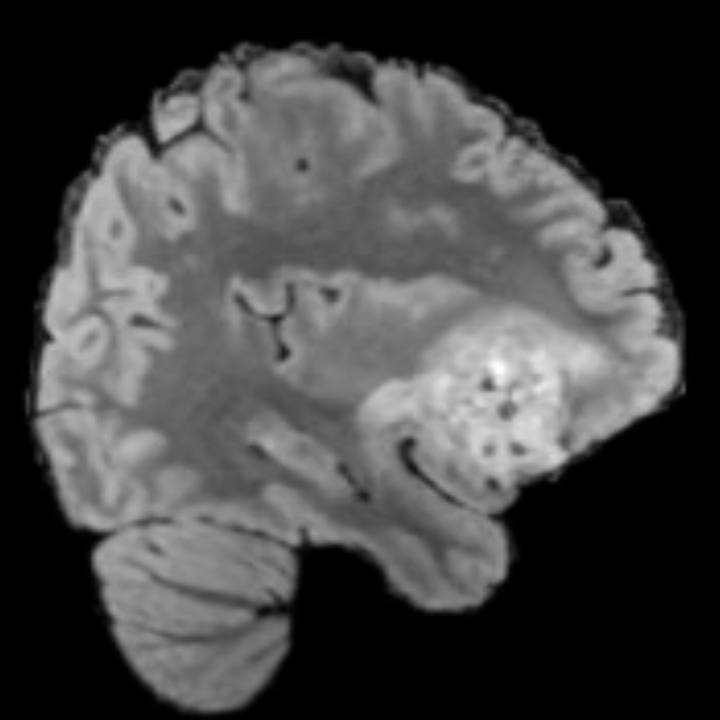

Tumour Information Preservation. For the brain tumor segmentation, we use a Swin UNETR model[27, 70], trained with random rotation, and intensity as data augmentation. In Figure 5, we highlight the tumor profiles of the generated MRIs compared to the ground truth tumour profile. In the test set with human ground-truth annotations (), the real MRI Dice score is 85.15 while the generated MRIs from a single slice have a dice score of 83.09. This shows how the generated MRIs indeed preserve the tumor information and can act as an affordable and informative pseudo-MRI, before conducting an actual costly MRI examination in hospitals.

B.4 Tumour Information Preservation

On the test set with human ground-truth annotations (), the brain volumes generated from single slice input preserve the volume of the different tumour components (paired t-test, for all 3 classes) (see Table 3). The real MRI Dice scores are put for reference to our generated MRIs. X-Diffusion outperforms baselines TPDM [36] and ScoreMRI [18] in tumour preservation (see Table 3 and Figure 12). We ran experiments comparing the tumour segmentation Dice Score varying X-Diffusion configurations. The multi-slice input X-Diffusion achieves a marginally better Dice Score than the single-slice input model (83.47 83.09). We also ran experiments with slice input used for volume reconstruction intersecting or not with tumour. We observe on average a drop of 6% Dice Score (see Table 3). Further away from the tumour the input slice for volume reconstruction is selected, and we observe a linear decrease in tumour segmentation Dice Score with the lowest value of 77.21 Dice Score (see Figure 15).

This shows how the generated MRIs indeed preserve the tumour information and can act as an affordable and informative pseudo-MRI, before conducting an actual costly MRI examination in hospitals. Given that our model has been trained on brain scans all with tumours, we expect to see hallucinations of tumours in healthy scans. We report two cases of failure of our model in Figure 16. Hallucinations of tumours on healthy samples represent 2% of the test set.